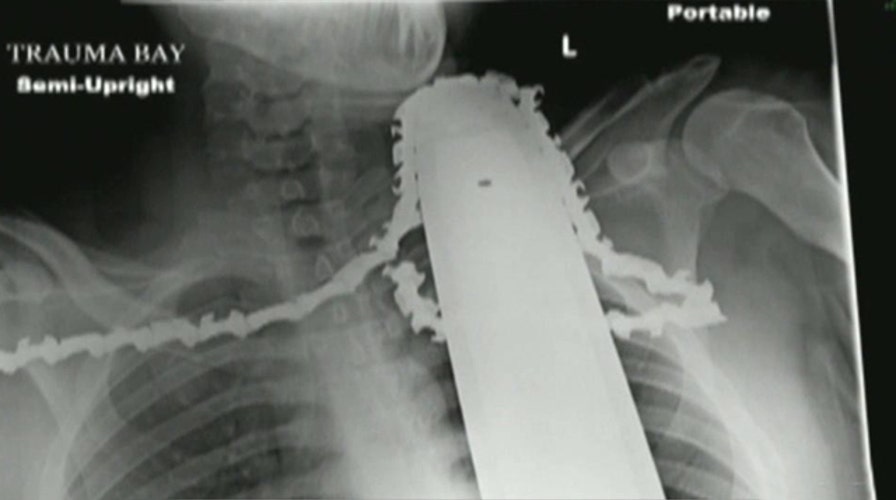

Pennsylvania man survives scary accident